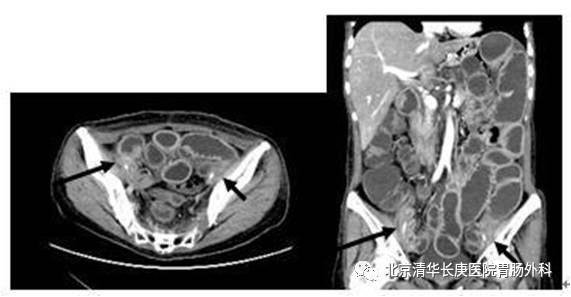

对于结直肠和小肠的狭窄部位的确定是手术主要解决的问题,因此通过造影和 CT可以综合准确判定。

或者受损伤肠管与髂血管、输尿管等重要脏器、血管粘连固定也为手术风险提前预警做了精准的术前评估,可以在术前进行输尿管支撑管的放置预防副损伤。